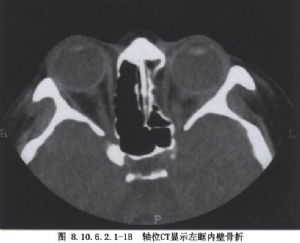

2.X线及CT检查可以证实眶底骨折的部位、形态、范围、有无眶内容脱出及是否合并有眶内、外、上壁骨折者。